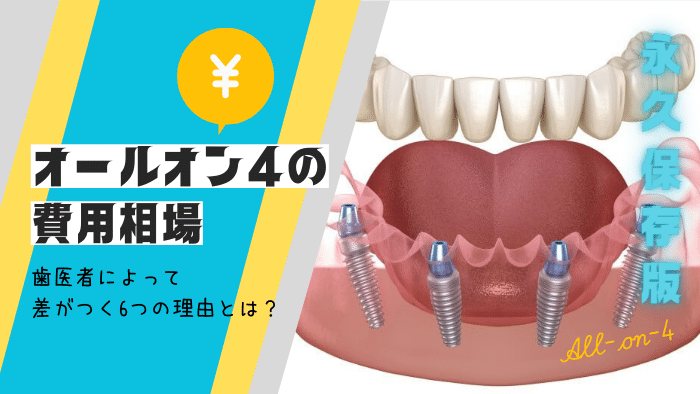

1-1:オールオン4とオールオン6で費用が異なるのはなぜ?

オールオンには、

- オールオン4:インプラントを4本埋め込む

- オールオン6:インプラントを6本埋め込む

があり、費用はオールオン4のほうが安くなっています。

それなら、最初から費用が安いオールオン4を選びたい!

と思われる患者さまも多いかと思いますが、実はそれぞれ以下のように適正条件が異なるのです。

- オールオン4:費用が安く、顎骨がしっかりしている方向け

- オールオン6:費用は高くなるが、顎骨が少ない方も長期的な耐久性を期待できる

そのため、オールオン4とオールオン6については、単純な治療費だけではなく患者さまのお口の中の状態に合わせて、担当医と相談した上で治療法を選ぶのがおすすめになります。